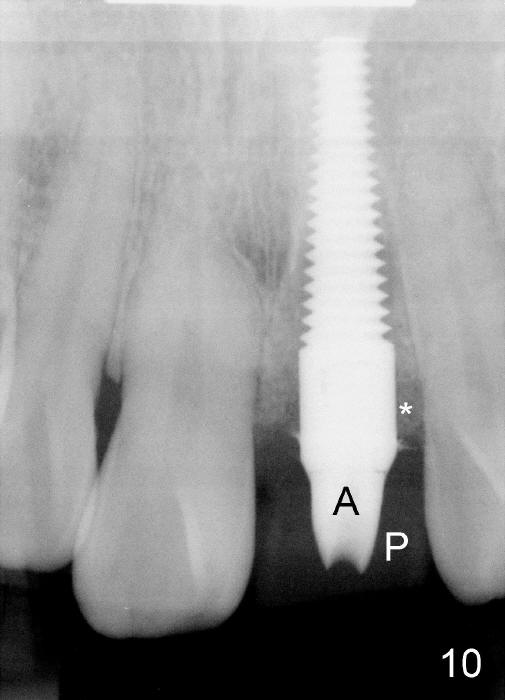

Bone expansion allows the implant (Fig.9 I) to have primary stability (insertion torque between 50 and 60 Ncm), since the cortex of the incisive canal is apparently intact. Allograft is placed in the labial gap (Fig.10, 11 *) following installation of the abutment (A). Finally an immediate provisional (Fig.10,12 P) is cemented. Fig.13,14 are taken 8 days postop. The patient returns 3 months postop (Fig.15,16). Osteointegration appears to have occurred (Fig.15 arrowheads) and is more obvious 9 months postop (Fig.17).